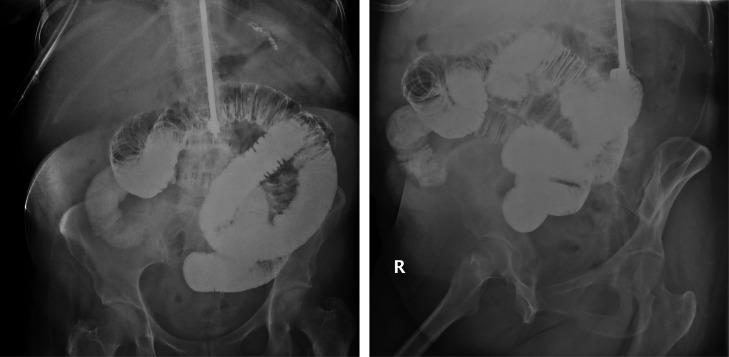

Complete small bowel obstruction without intussusception due to a submucosal lipoma.

Submucosal Lipoma Causing Small Bowel Intussusception.

Submucosal Lipomas Causing Intussusception and Small Bowel Obstruction: A Case Report.

A case of colonic intussusception and obstruction secondary to giant colonic lipoma.

Ileoileal intussusception in unspecific recurrent abdominal pain in adult: A case report.

Sonographic findings in intussusception caused by a lipoma in the muscular layer of the colon.

Novel surgical approach without bowel resection for multiple gastrointestinal lipomatosis: A case report.